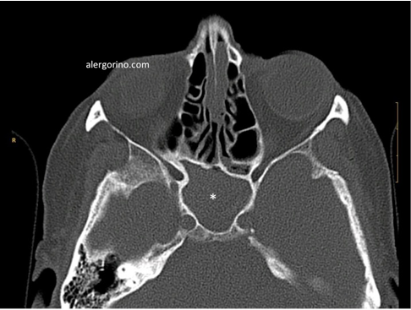

El diagnóstico se realiza mediante la historia clínica y una endoscopia nasal que proporcionan datos como la presencia de pólipos, la descarga mucopurulenta y el edema o la obstrucción de las áreas de drenaje de los senos paranasales. Si no se produjera una respuesta al tratamiento médico se evalua la situación de los senos paranasales mediante una tomografía computarizada (TC).